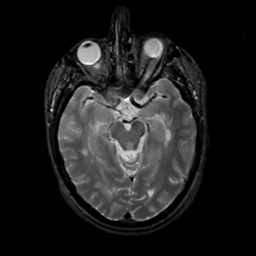

MR Study #14, June 2, 1991 -- Slice #20